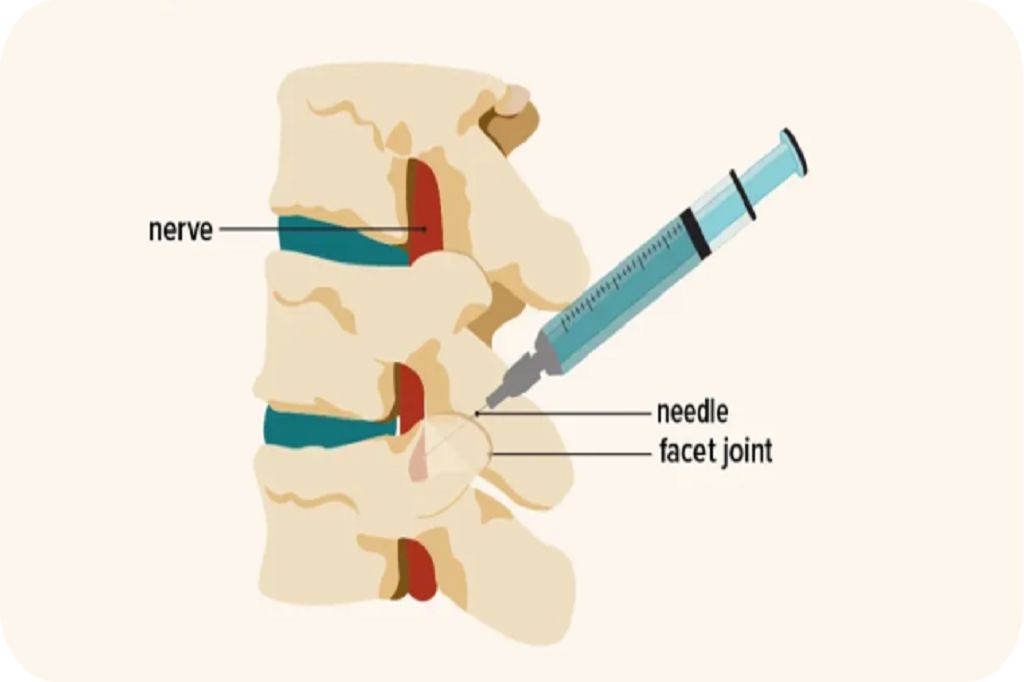

Used to diagnose and treat pain from arthritis in the small joints of the neck. This injection can help confirm the joint as the pain source.

A two-step process: First, a Medial Branch Block (a diagnostic test) confirms the exact pain source. If successful, Radiofrequency Ablation is then used to provide long-term relief.